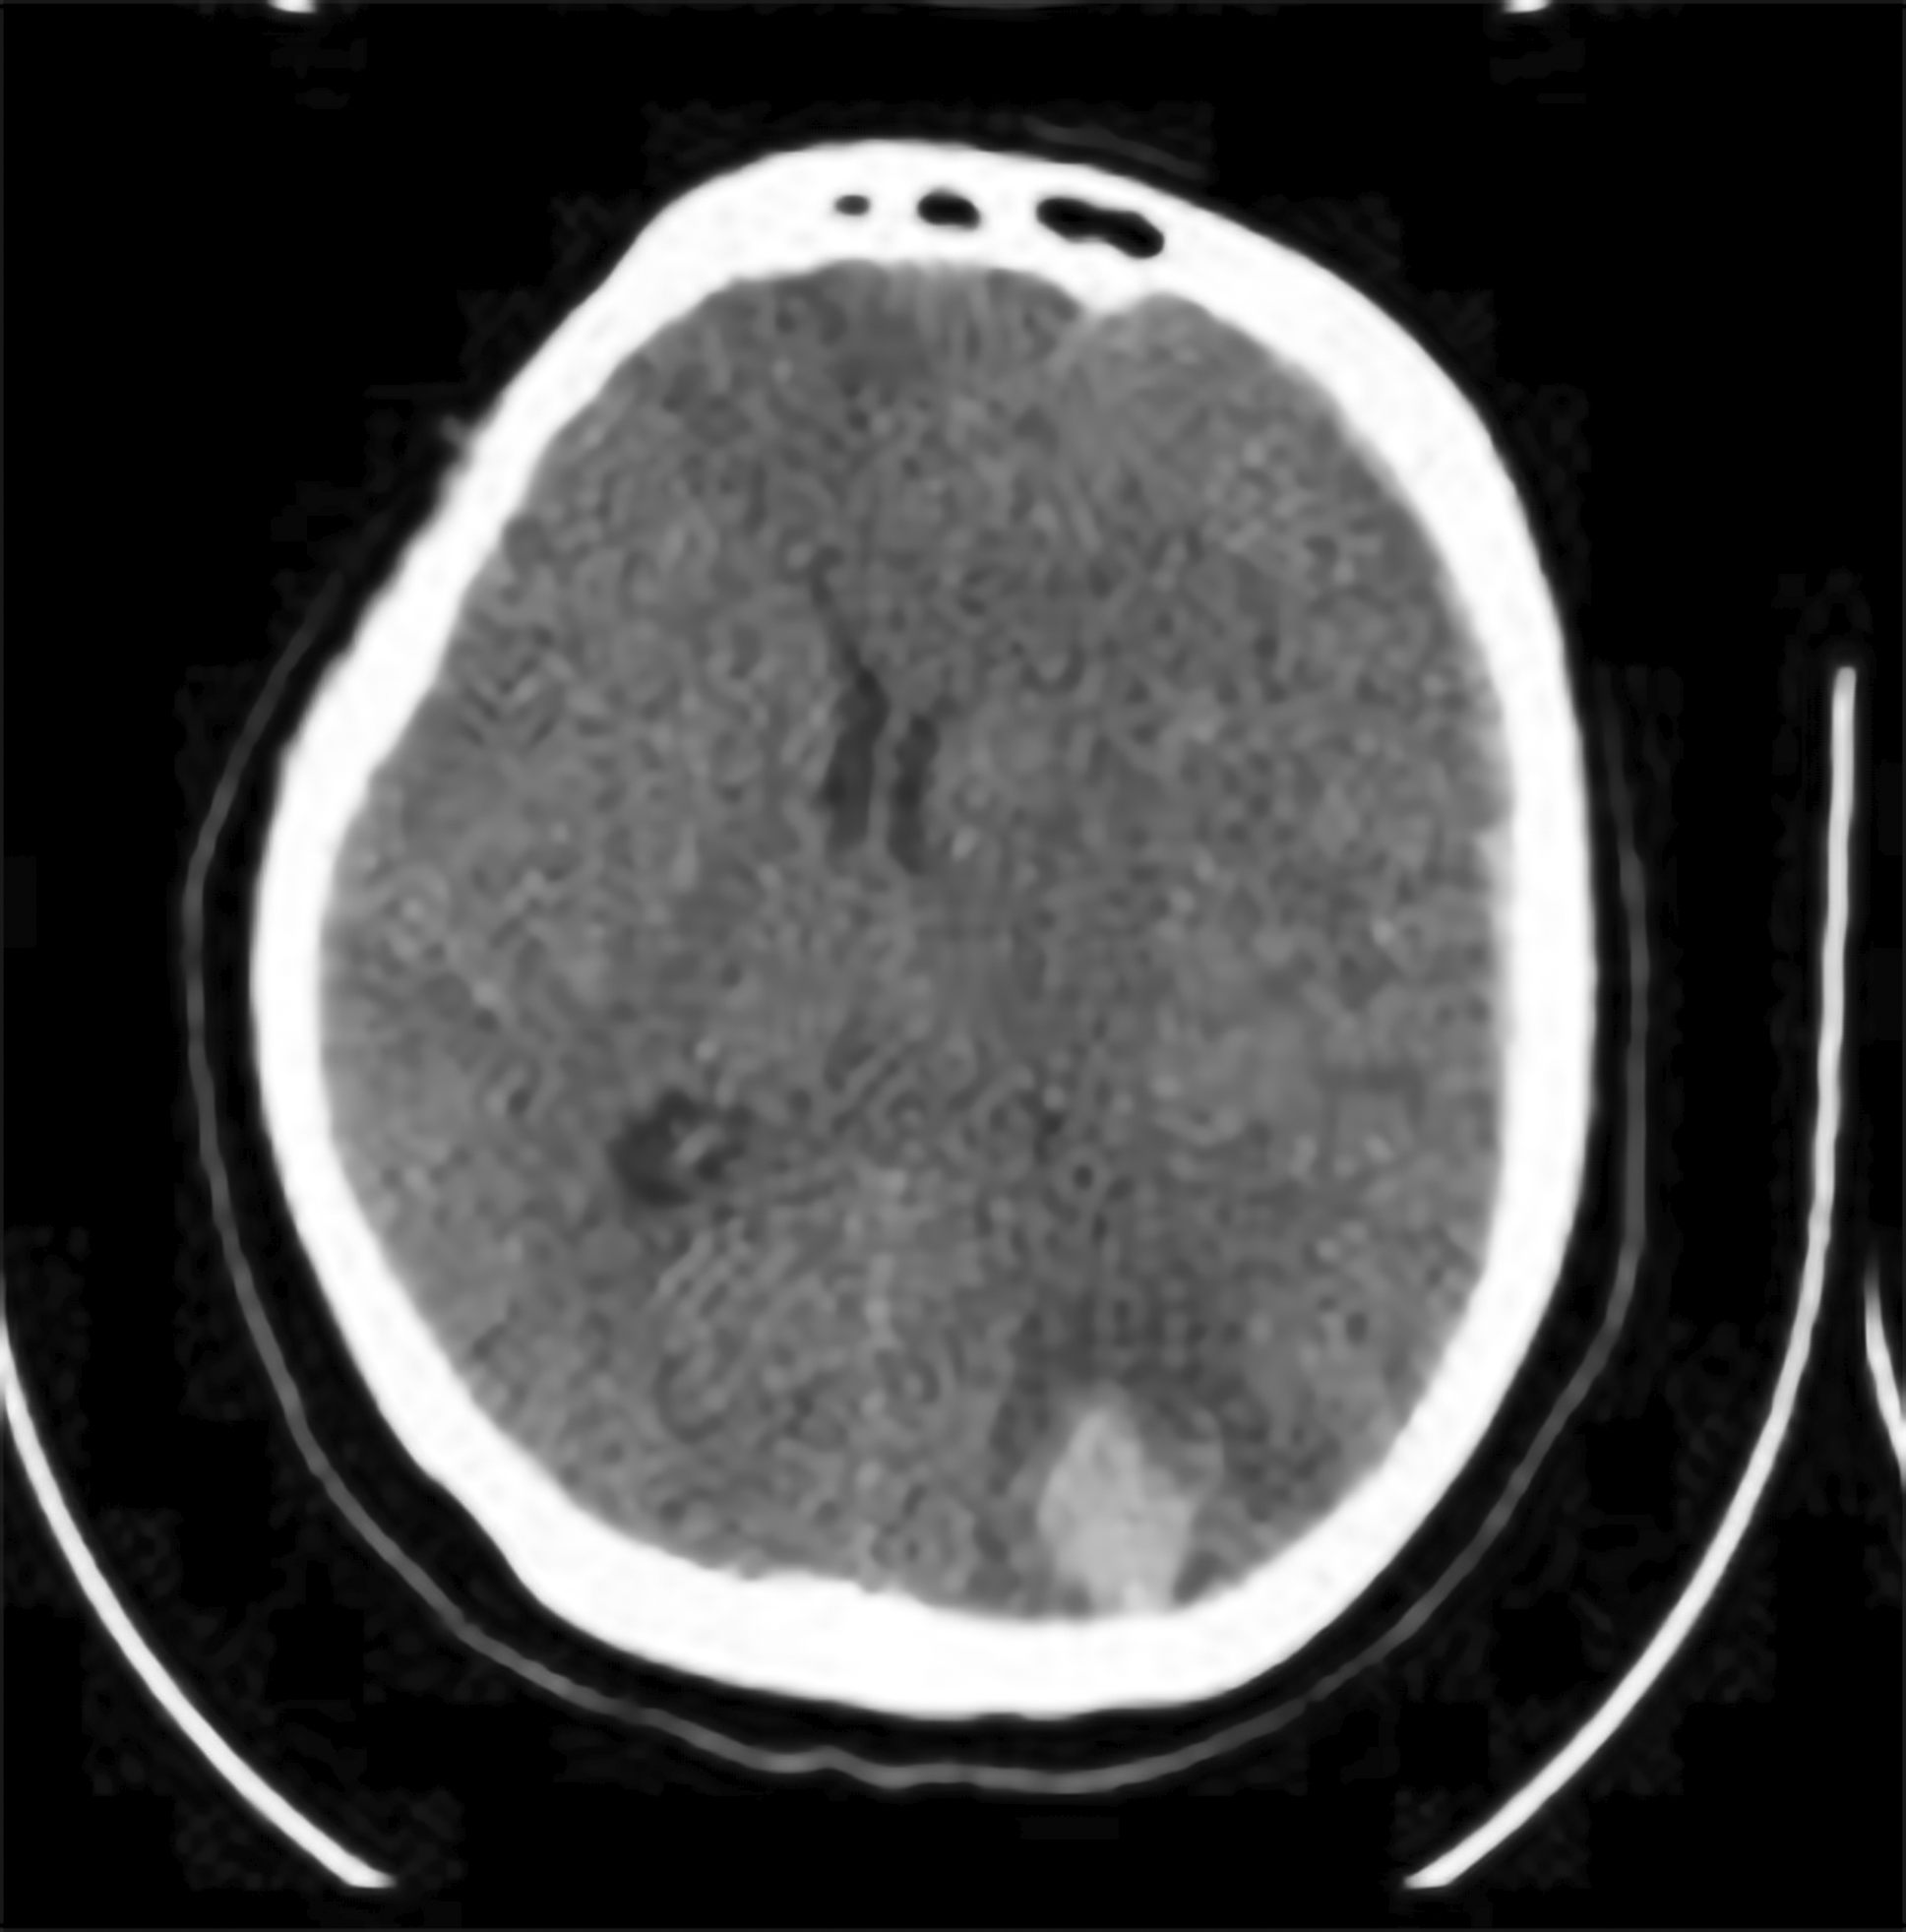

An emergency non-contrast head CT scan was performed immediately following the neurological decline. This revealed a remote haemorrhagic event, distant from the original operative site. The findings included a 20cc left parietal intracerebral haematoma and a concomitant acute left frontoparietal subdural haematoma. The combined mass effect resulted in a midline shift of over 5 mm ( Figure 4).

Medical therapy to control intracranial pressure (ICP) was initiated, consisting of intravenous mannitol and head-of-bed elevation. Following this conservative management, her level of consciousness progressively improved over the next three days. However, the patient suddenly became aphasic and could not understand any command on day 13th postoperatively ( Figure 5). Another head CT scan was performed and revealed partially resolved ICH at the parietal lobe with slight additional thickness of subacute SDH and midline shift to the right. Conservative management with mannitol and tranexamic acid was continued. The patient showed clinical improvement after 2 days and discharged from hospital at day 18th postoperatively. The three-month postoperative MRI confirmed gross total resection of the meningioma and complete resolution of the remote haemorrhage, without evidence of any vascular malformation ( Figure 6).